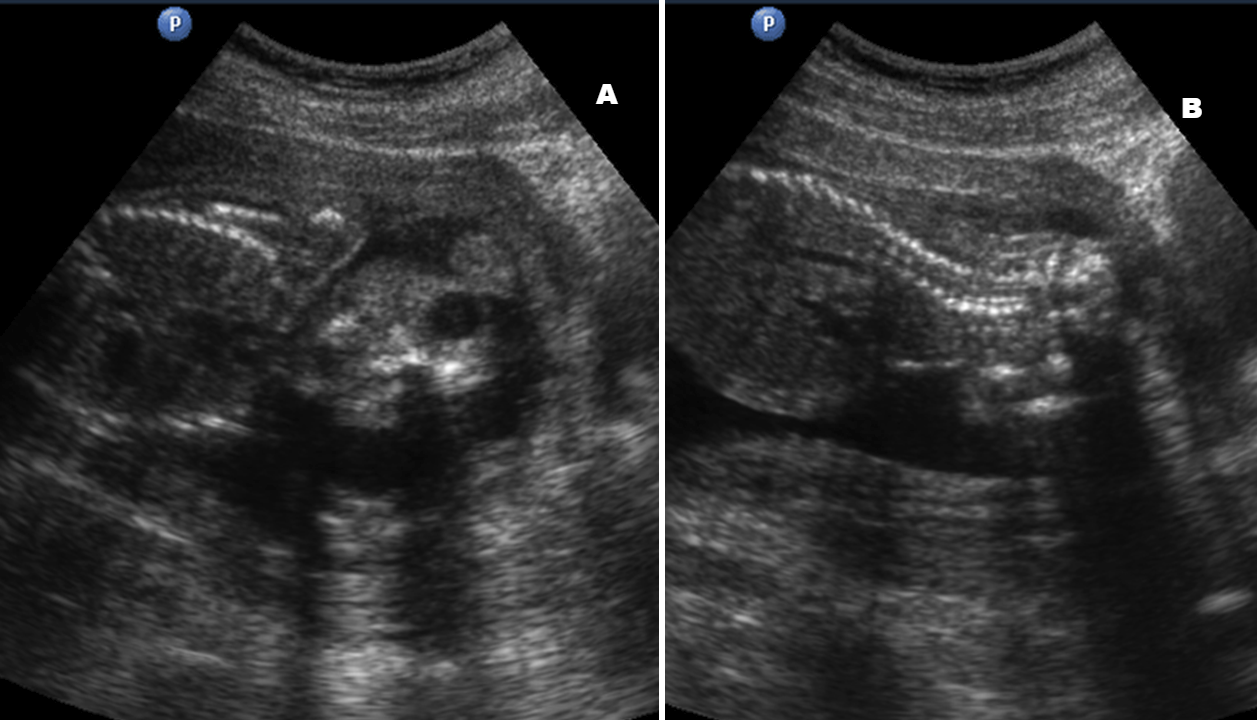

Анэцефалия